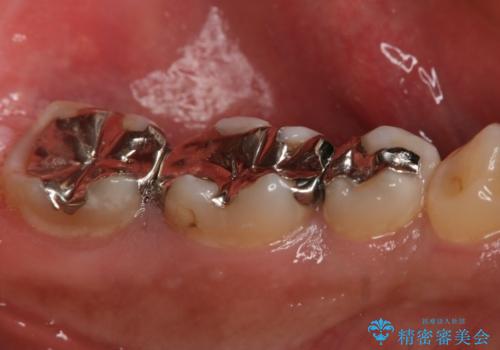

フルジルコニアクラウンによる銀歯のやり変え

- 99000円(フルジルコニアクラウン+仮歯)費用は治療当時の料金となります

う蝕が深く切削量が多くなりましたが痛みなどは起きなかったので、予定通りフルジルコニアクラウンでの治療で進めました。